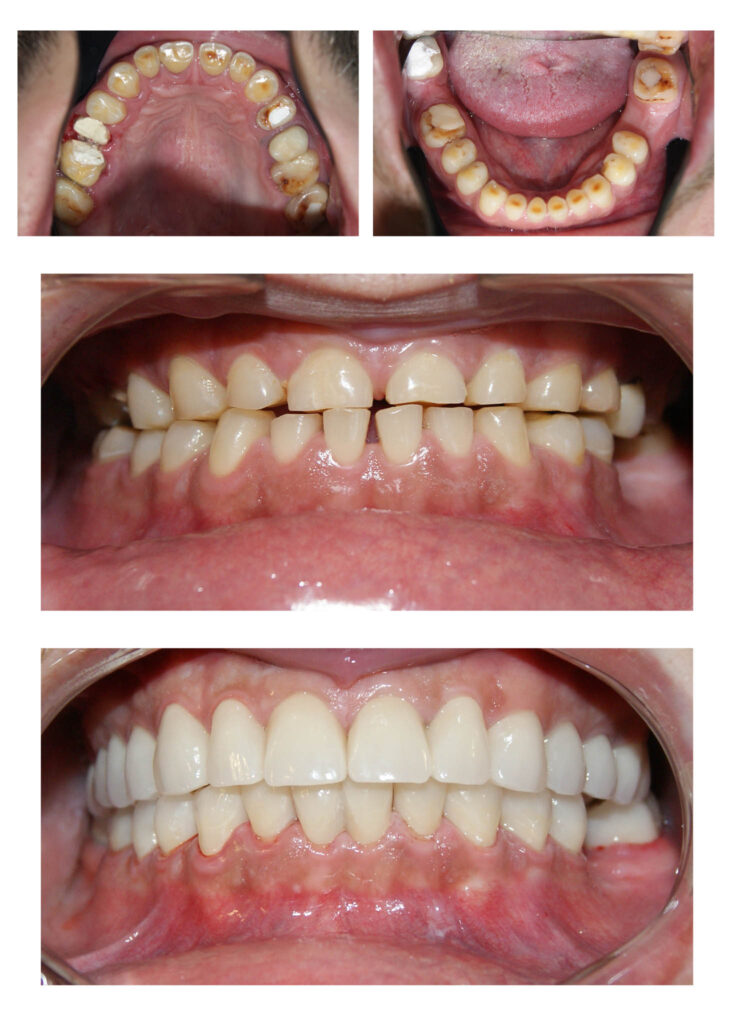

Reabilitare orală complexă cu redimensionarea dinților cu grad accentuat de uzură. A fost necesară o soluție de provizorat de 6 luni de zile în care am verificat dacă pacientul se poate adapta cu înălțarea ocluzală propusă de noi. Am realizat tratamente de canal și reconstituiri atât pentru înălțarea dinților, cât și pentru tratarea proceselor infecțioase active. Rezultatele sunt remarcabile atât din punct de vedere funcțional cât și estetic